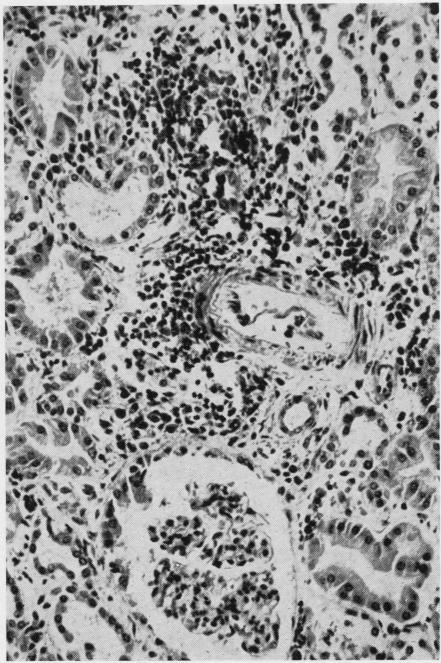

Distal tubular and proximal tubular necrosis in the kidneys of burned patients.